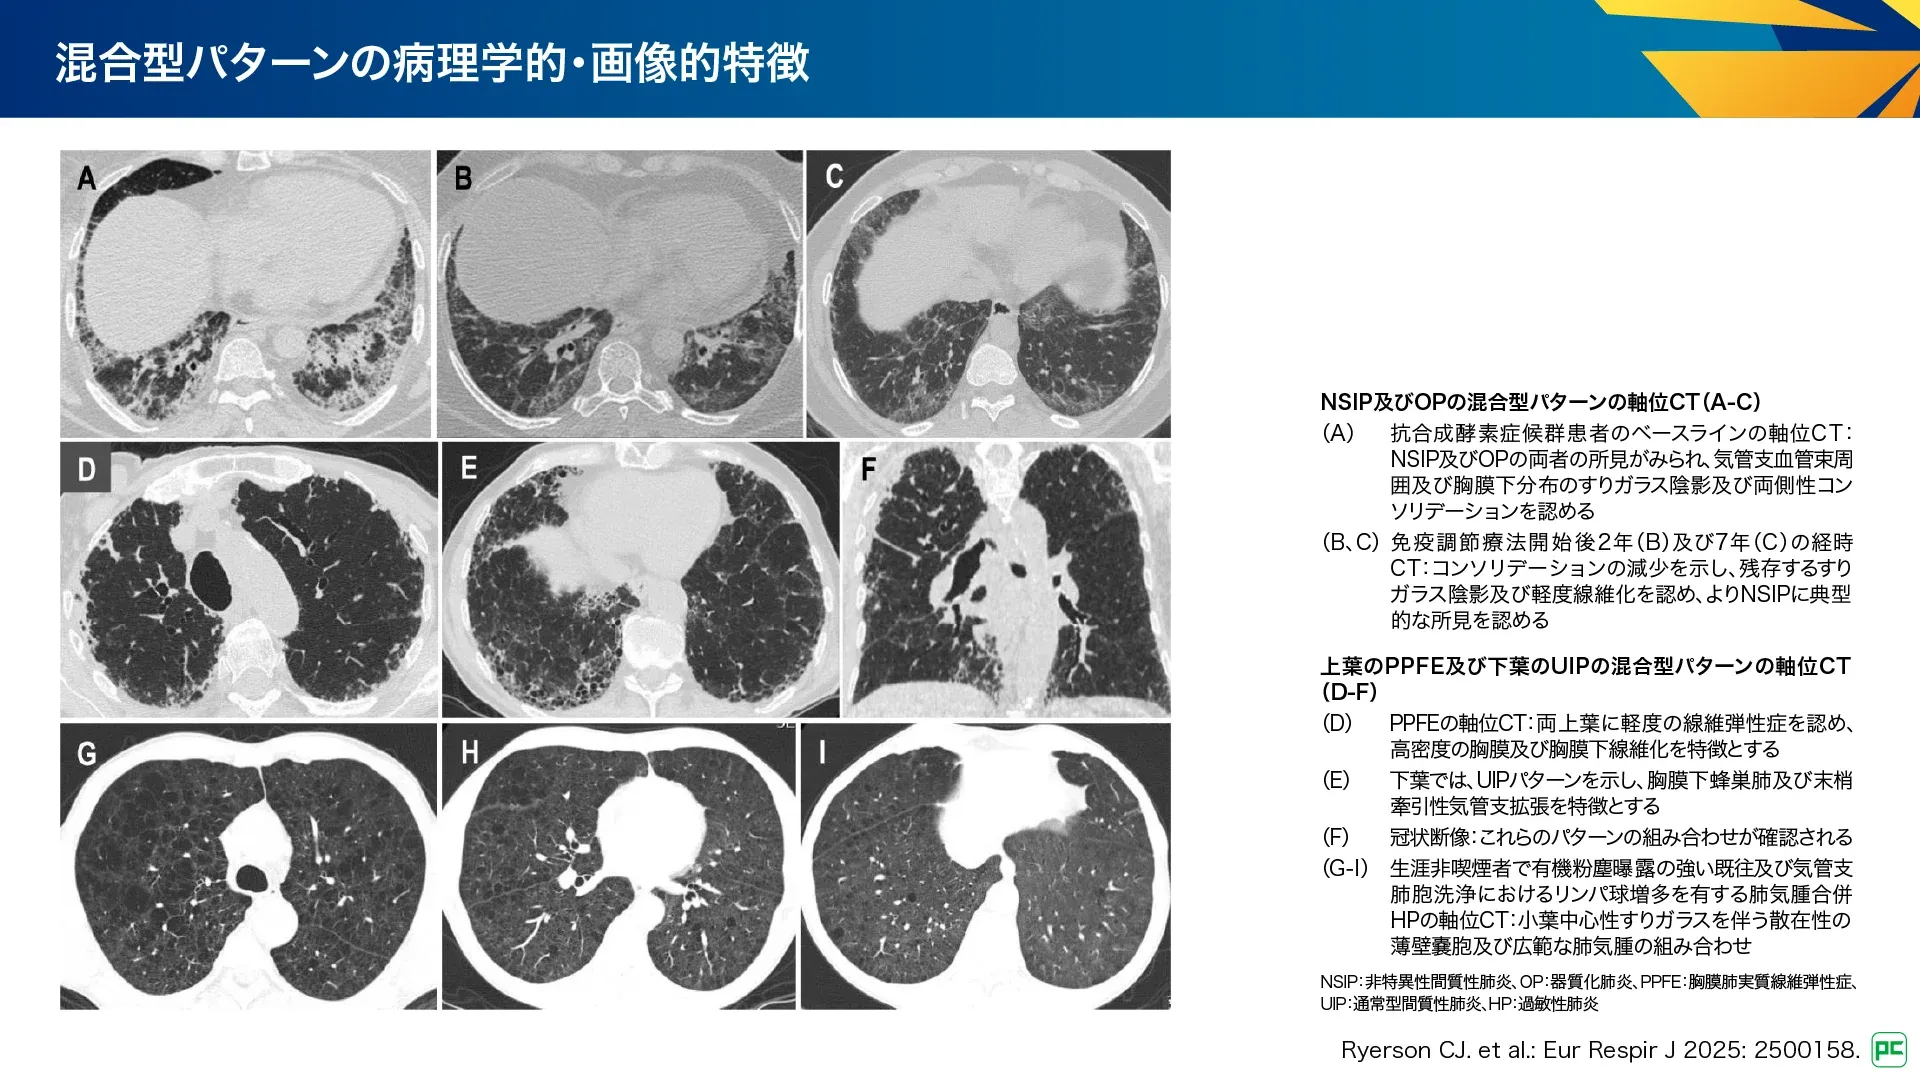

D. 混合型パターン

複数の異なるパターンの組み合わせで発症することがあり、混合型パターンとされています(図25、図26)。混合型パターンを有する患者は、診断や管理が難しく、多分野の専門家による慎重な評価を行うことで、異なる領域の所見を統合して診断につなげたり、治療方針や予後を決める主要なパターンを特定できます。

図25

図26

PPFEの所見を有する患者の最大50%はUIPパターンを有しています。また、IPFにおいてもPPFEの特徴がよくみられ、通常はIPFとして診療されます。PPFEとUIPはCTD-ILD、HPなどで他のパターンと混合することがあり、通常より予後不良であることを示唆します。また、特発性炎症性筋疾患(IIM)では、NSIPとOPの混合が報告されるなど、様々な組み合わせが示されています(図26)。